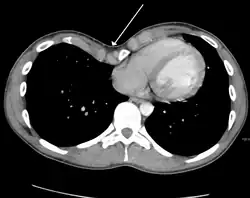

Many scales have been developed to determine the degree of deformity in the chest wall. Most of these are variants on the distance between the sternum and the spine. One such index is the Backer ratio which grades severity of deformity based on the ratio between the diameter of the vertebral body nearest to xiphosternal junction and the distance between the xiphosternal junction and the nearest vertebral body.[20] More recently the Haller index has been used based on CT scan measurements. An index over 3.25 is often defined as severe.[21] The Haller index is the ratio between the horizontal distance of the inside of the ribcage and the shortest distance between the vertebrae and sternum.[22]

Chest x-rays are also useful in the diagnosis. The chest x-ray in pectus excavatum can show an opacity in the right lung area that can be mistaken for an infiltrate (such as that seen with pneumonia).[23] Some studies also suggest that the Haller index can be calculated based on chest x-ray as opposed to CT scanning in individuals who have no limitation in their function.[24]

Pectus excavatum requires no corrective procedures in mild cases.[25] Treatment of severe cases can involve either invasive or non-invasive techniques or a combination of both. Before an operation proceeds several tests are usually performed. These include, but are not limited to, a CT scan, pulmonary function tests, and cardiology exams (such as auscultation and ECGs).[26] After a CT scan is taken, the Haller index is measured. The patient's Haller is calculated by obtaining the ratio of the transverse diameter (the horizontal distance of the inside of the ribcage) and the anteroposterior diameter (the shortest distance between the vertebrae and sternum).[27] A Haller Index of greater than 3.25 is generally considered severe, while normal chest has an index of 2.5.[22][28][29] The cardiopulmonary tests are used to determine the lung capacity and to check for heart murmurs.[30]